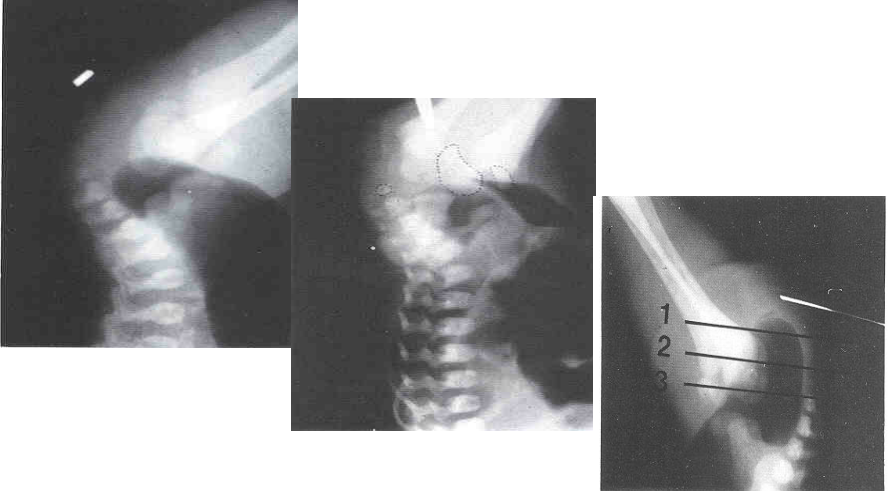

▷ 钡剂灌肠(Barium Enema)

- 无神经节细胞段与近端结肠口径差别、扩张段、狭窄段及移行段改变

- 结肠炎时粘膜锯齿状改变

- 24小时后钡剂滞留

操作简单,方法普及

新生儿确诊率80%

短段型不易诊断

X线征象:出生12h后进行倒立侧位摄片(时间、体位、按摩、肛门标志)